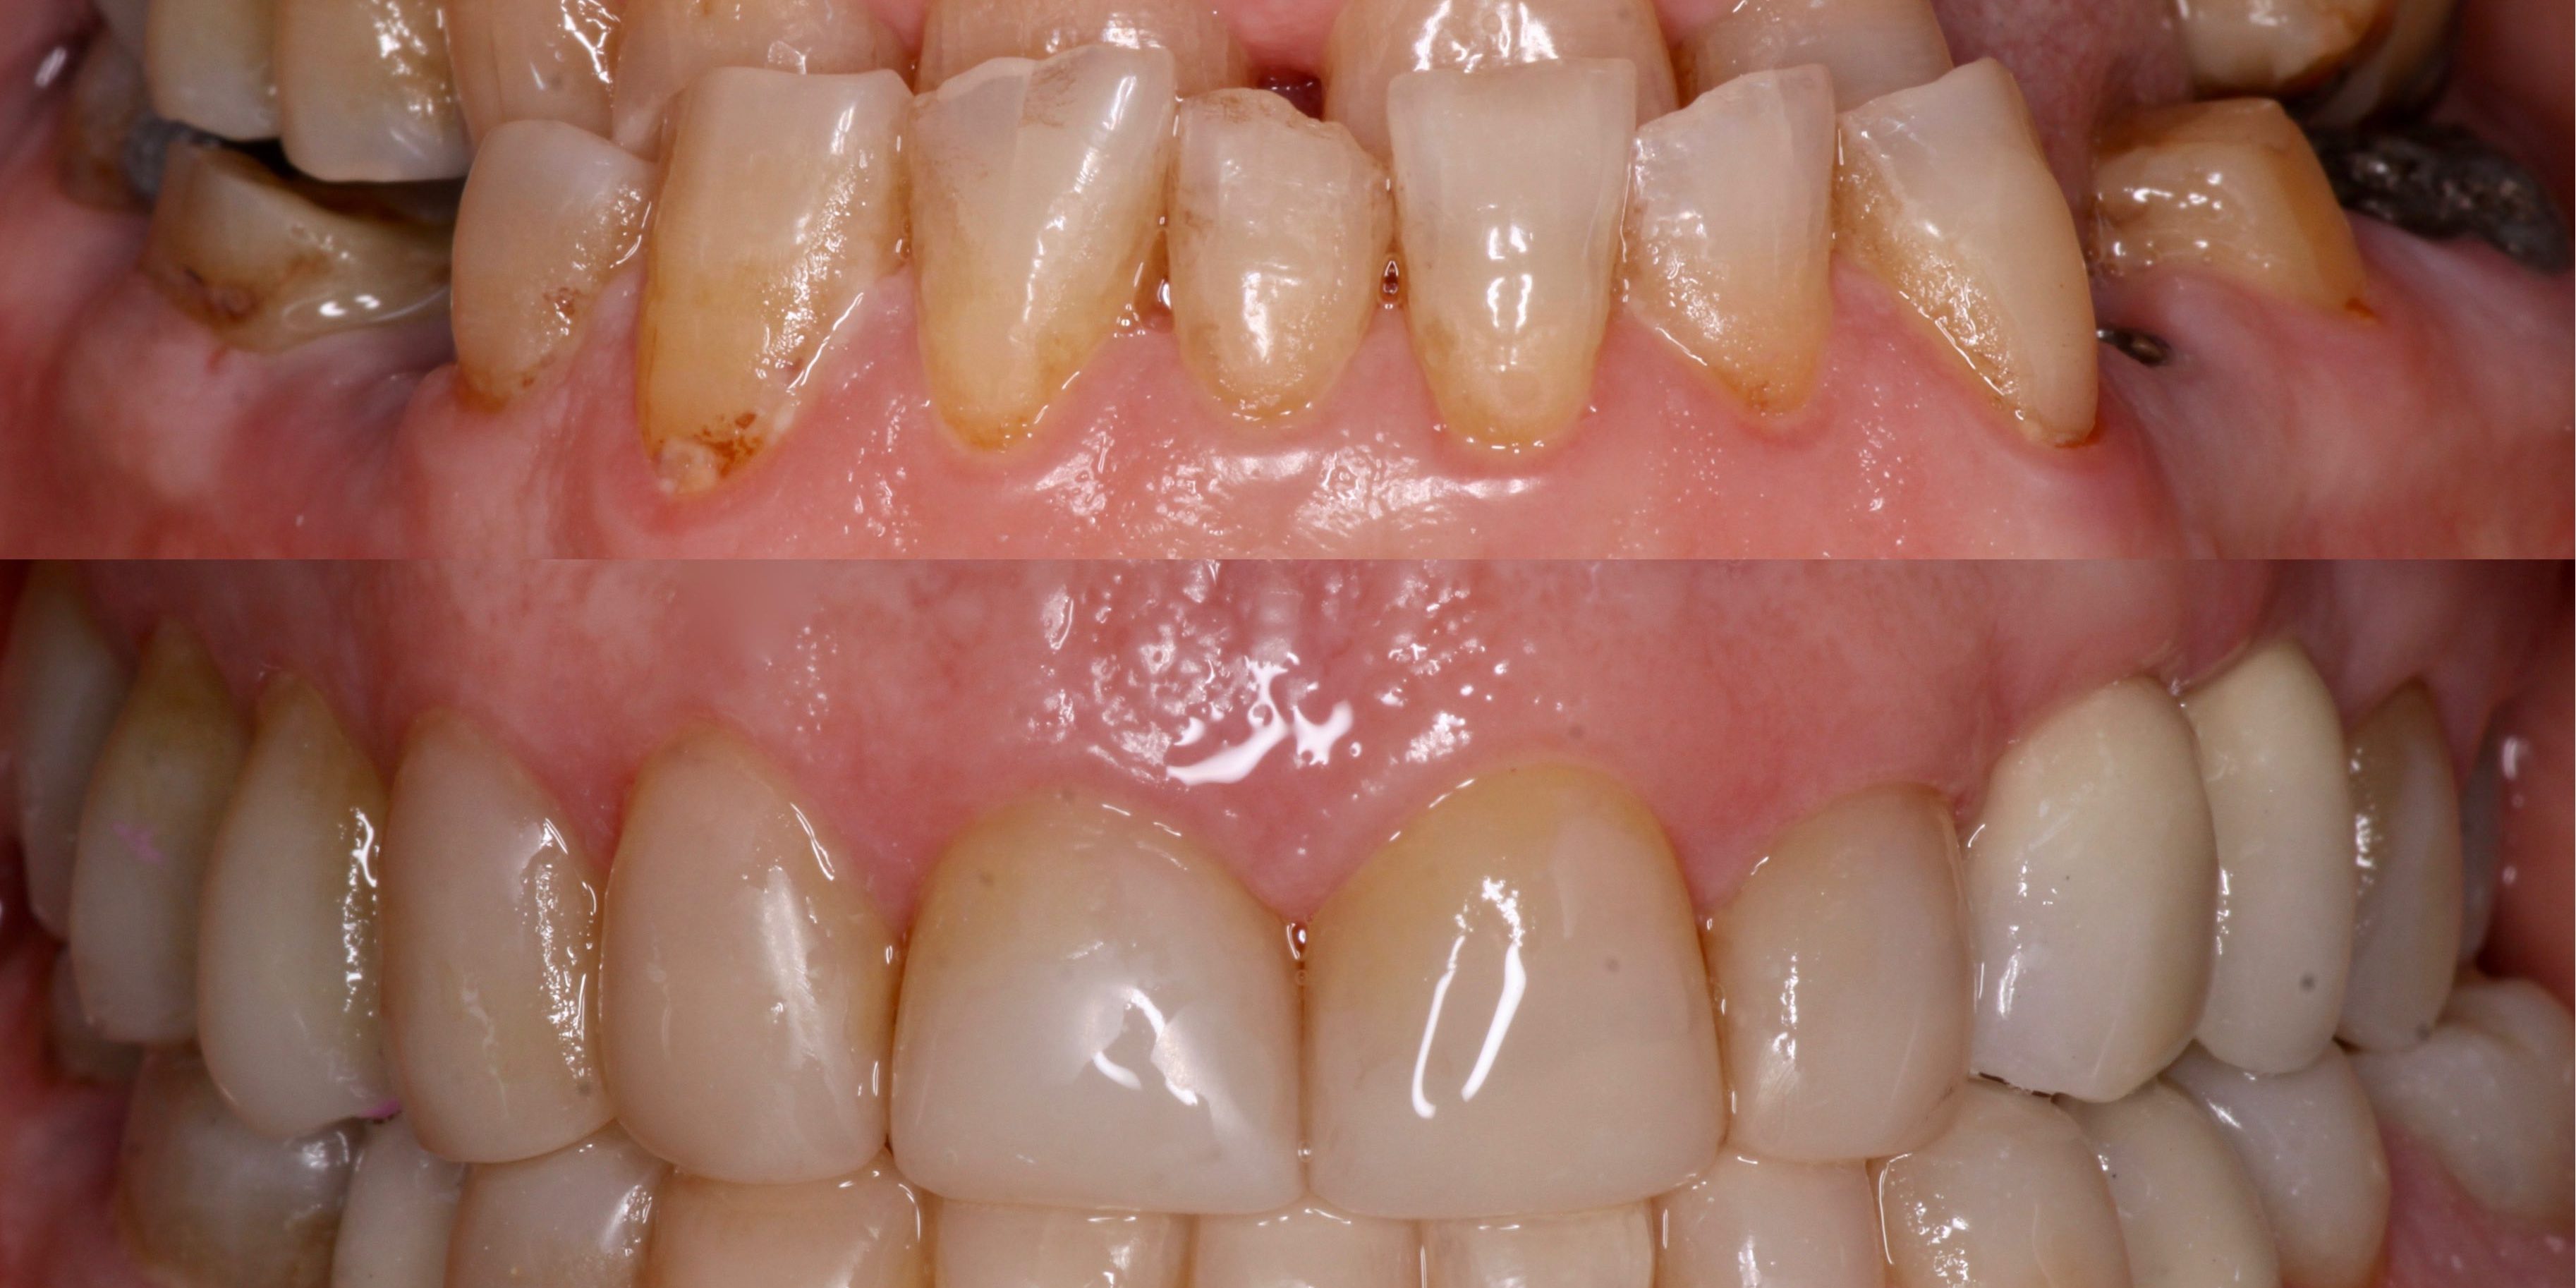

Paciente de 73 años que acude con mordida en tijera anterior y gran destrucción de piezas dentarías y ausencia de varias de las mismas. Se procede a una rehabilitación mínimamente invasiva con composite de manera adhesiva, donde las piezas restantes prácticamente no necesitan tratamiento y nos asegura reversibilidad si hubiera algún problema en el futuro. Como se puede observar, solo aumentando la dimensión vertical es posible corregir en algunos casos grandes maloclusiones. Para la sustitución de las piezas ausentes se procedió a la colocación de implantes dentales endoóseos sobre los que se pusieron coronas cerámicas. El tratamiento fue realizado por el Dr. Ramón Susín (rehabilitación adhesiva y protésica) y el Dr. Plaza (colocación de los implantes) .

- Inicial Intraoral

- Final Intraoral